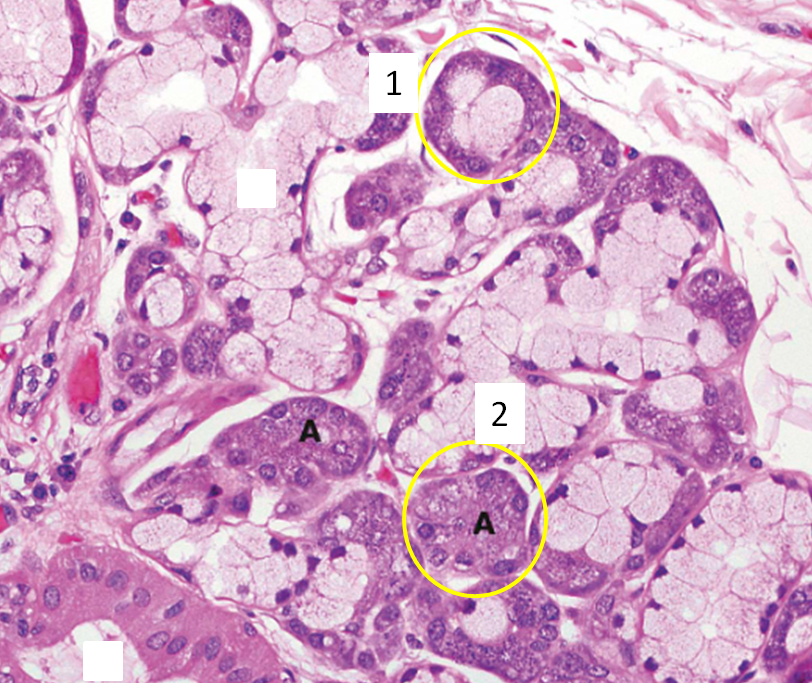

Glândulas exócrinas (1 misto; 2 ducto(epitélio cúbico simples; 3 seroso).

Tipo secreção (1: ácino misto; 2 ácino seroso)